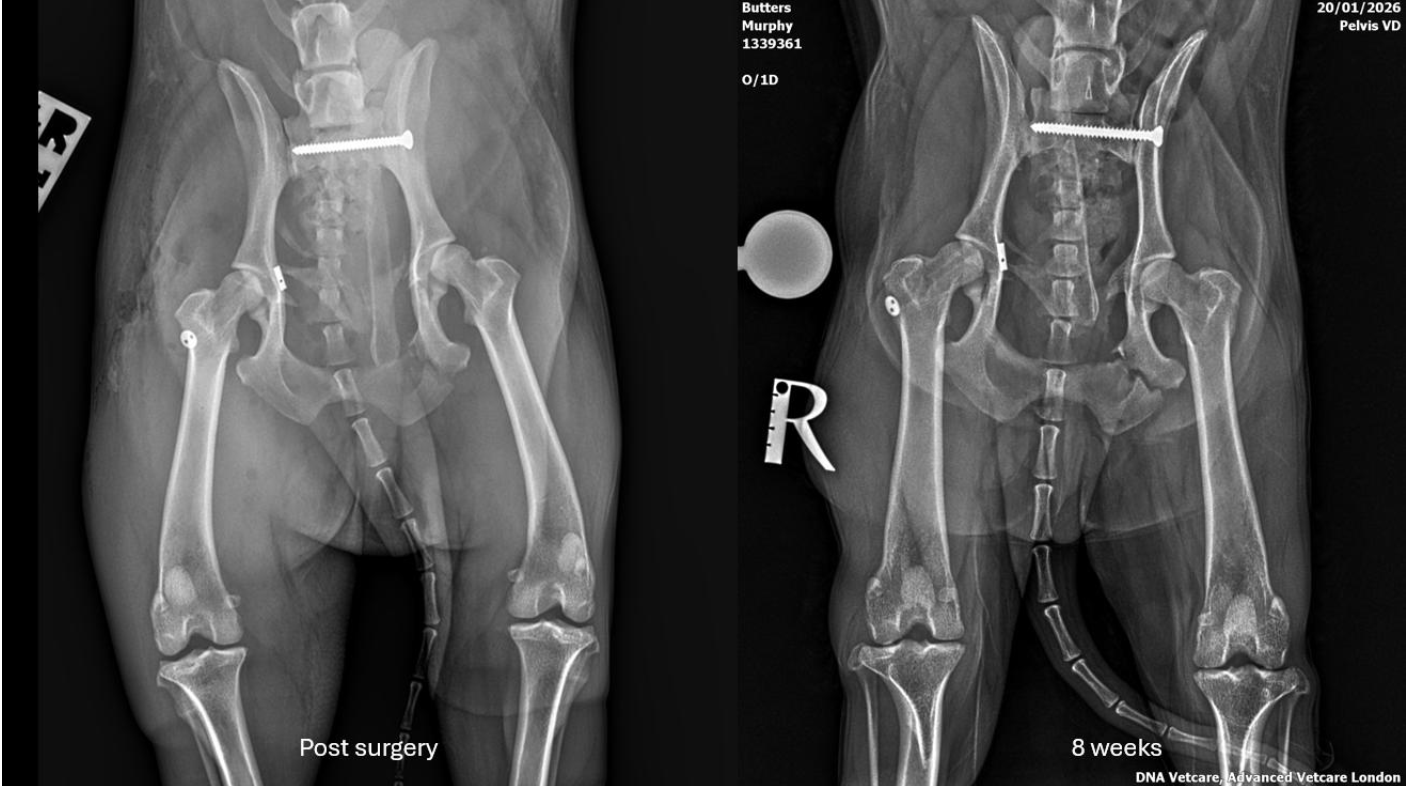

Starting at the top, the team repositioned the dislocated sacroiliac joint and secured it with a screw - a technique that compresses the joint surfaces together as the screw tightens, providing maximum stability. Murphy recovered well from anaesthesia and was transferred to intensive care.

Five days after the accident we were able to address Murphy’s hip dislocation.

Hip dislocations are classified by which direction the femoral head (ball) has moved from the socket. Murphy's was a craniodorsal luxation (upward and forward) - the most common type. Examination under anaesthesia revealed a type C joint capsule tear, meaning the fibrous capsule surrounding the hip had torn extensively.

Murphy's prognosis is cautiously optimistic. Walking just six days after such devastating injuries is remarkably encouraging. However, the true test comes over the following weeks and months as fractures heal, the toggle stabilises and extensive soft tissue damage resolves.